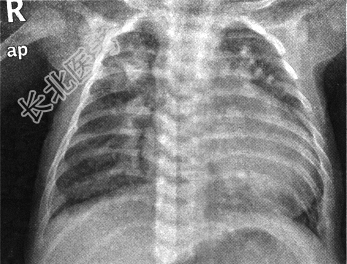

- [材料题] 患儿,男,55天,因"发现紫绀半月"入院。病史:足月顺产,满月后进食、哭闹后口唇及手指处紫绀,进奶欠佳,吃吃停停。查体:体重4.1kg,体温37.2℃,心率136次/分,律齐,SpO 273%,上肢血压78/49mmHg,下肢血压90/50mmHg。听诊心音亢进,心前区杂音不明显,肝肋下刚触及。胸部X线平片见下图。

- 多项选择题1.X线平片的发现包括( )

A、心胸比例增大

B、心胸比例减小

C、肺血减少

D、肺充血

E、内脏心房反位

F、胸腔积液